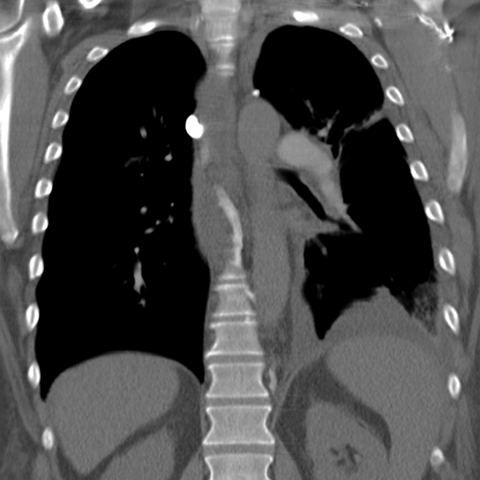

Pleural Effusion, Small to Moderate [5 of 5]